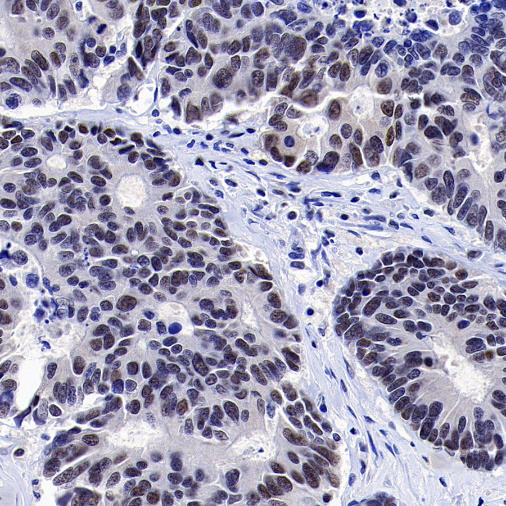

Positive staining

IHC shows positive staining in paraffin-embedded human colon

IHC shows positive staining in paraffin-embedded human testis

Negative staining

IHC shows negative staining in paraffin-embedded human colon cancer

IHC shows negative staining in paraffin-embedded human pancreatic cancer